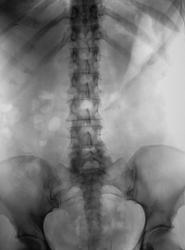

Пациентка направлена на внутривенную урографию. Какие будут мнения?

Слабое контратирование левой почки, мочеточник прослеживается до уровня крестца. Тень в проекции дистального отдела левого мочеточника, возможно конкремент.

Согласен. Просмотрел. Значит, остаётся гидронефроз справа, возможно стриктура или врождённое высокое отхождение мочеточника.

Признаки нарушения оттока из правой ЧЛС симнительной этиологии))

На томограмах складывается ощущение, что справа видна значительно расширенная тень мочеточника? Особенно, если сравнить две половины. Точно сказать нельзя, потому что там m.psoas подобной конфинурации проходит.

Врожденное сужение ЛМС справа...вот и все....)))), а все остальное - следствие.